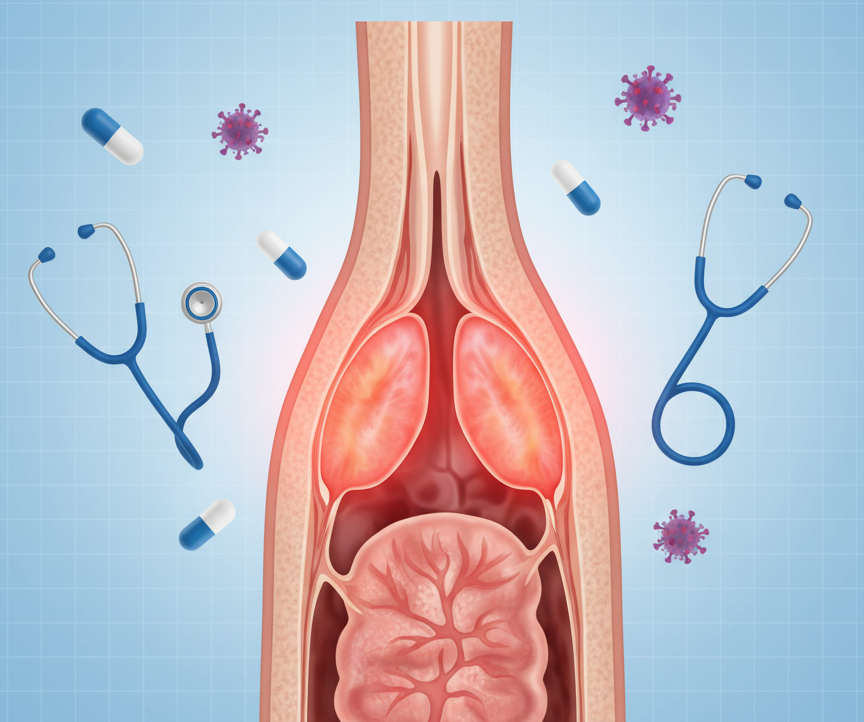

Throat Infection: Causes, Symptoms, and Smart Treatments

Throat infections are a prevalent health problem that can lead to throat pain, swelling, and…